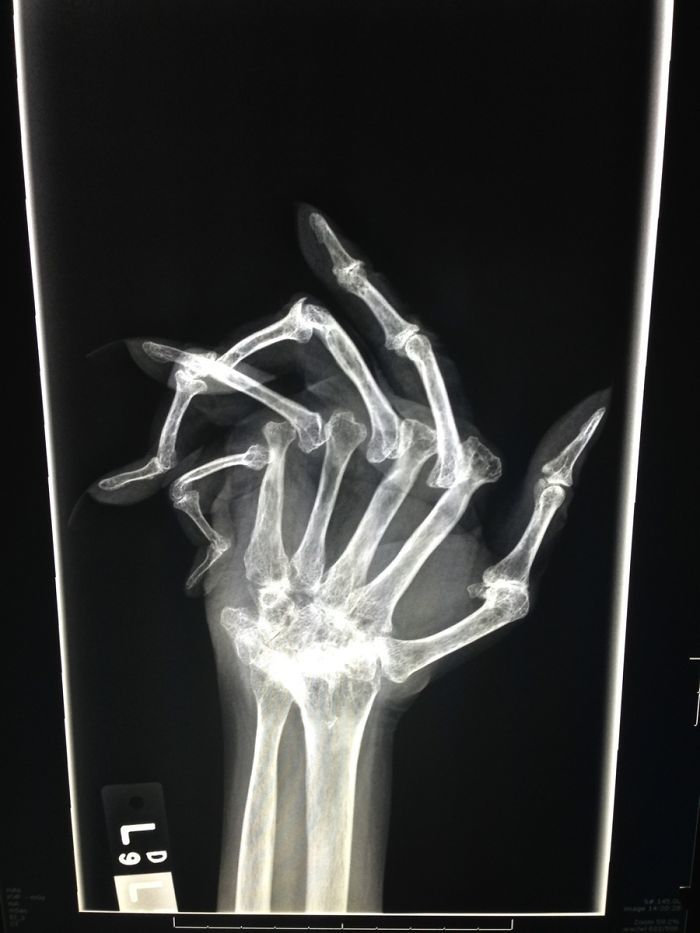

文章插图

晚期类风湿关节炎